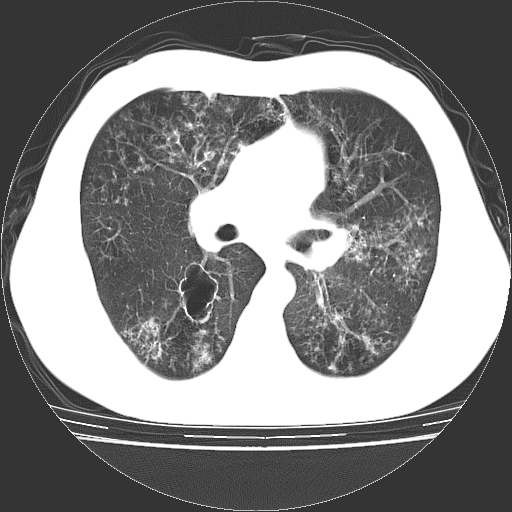

以下是引用zyx168在2006-12-4 15:30:00的发言:[br]经典!支气管肺囊肿并感染。

以下是引用dyqct在2006-12-4 17:11:00的发言:[br]典型的囊状支扩合并感染。

以下是引用liaoqiang在2006-12-4 16:12:00的发言:[br]局部肺叶内可见扩张的支气管壁,考虑为支扩。部份囊样影内有小液平和肺内散布斑片征影、小结节及纤维灶,提示支扩伴感染,且由于局部呈现有树芽征感染以结核可能性大。

以下是引用zhoucan076在2006-12-4 16:48:00的发言:[br]囊状支扩合并感染